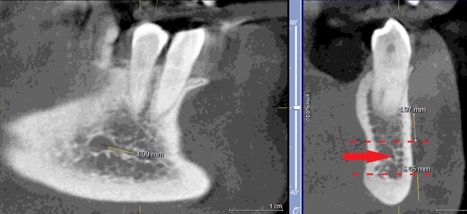

При измерении расстояния от резцовой петли до вестибулярной стенки нижней челюсти и её топографии в области правила «трёх пятёрок», выделено три положения канала, в котором проходит резцовая петля: канал прилежит, т.е. стенка канала образована кортикальной частью (рис 3), касается, т.е. имеет одну общую точку (рис 4) и не имеет общих точек.

Рисунок 3. КЛКТ Сагиттальныи и коронарныи реформаты переднего отдела нижнеи челюсти..jpg

Рисунок 3. КЛКТ Сагиттальный и коронарный реформаты переднего отдела нижней челюсти.

Стенка канала образована кортикальной частью кости.

Красная стрелка – «резцовая петля».

Красный пунктир – канал проходит в проекции участка правила «трёх пятёрок».

Рисунок 4. КЛКТ Сагиттальныи и коронарныи реформаты переднего отдела нижнеи челюсти..jpg

Рисунок 4. КЛКТ Сагиттальный и коронарный реформаты переднего отдела нижней челюсти.

Канал соприкасается с кортикальной частью кости (красная стрелка – резцовая петля).